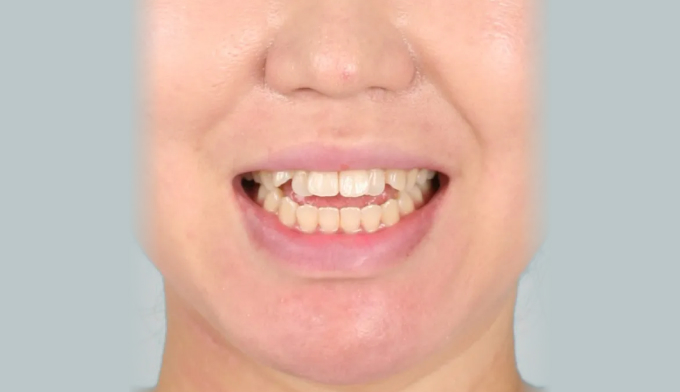

돌출입과 개방교합이 동시에 있는 경우에는 발치교정을 통해 앞니를 넣어주면 개방교합이 쉽게 개선됩니다. 이때 주의할점은 미소시 치아의 노출정도입니다. 또한 개방교합의 경우에는 재발 경향이 높기 때문에 주기적인 경과관찰이 필요하며 최종위치에 안정적으로 치아가 위치해있다고 판단이 들었을 때 교정치료를 종료하여야 합니다.

총 교정기간은 25개월입니다.